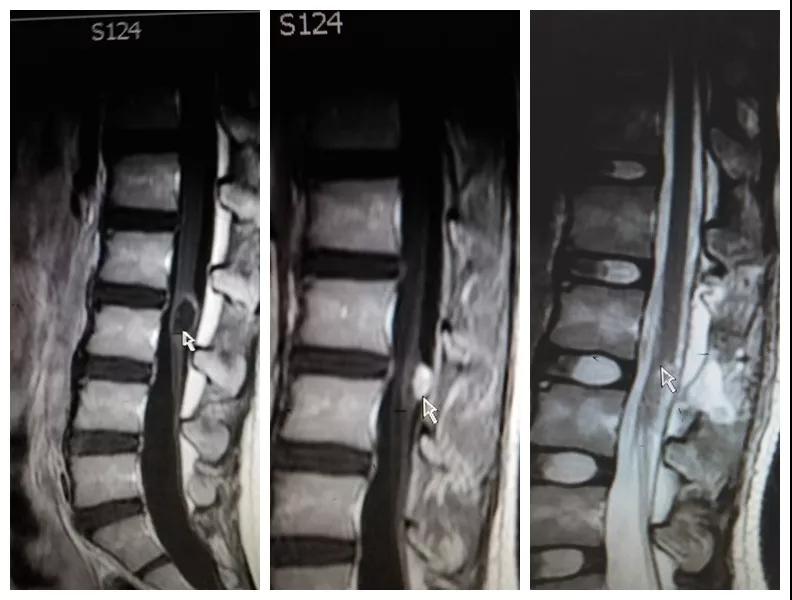

2018年8月,孩子母亲带着一线希望慕名找到21点玩法研究所 神经外科王占尧主任医师。王医生通过详细询问病史、查体、完善相关检查后,明确诊断患者为腰3椎管脊髓内畸胎瘤、硬脊膜外脂肪瘤、脊髓栓系综合症、骶尾部皮毛窦。王占尧耐心与家属沟通病情及手术方式,因手术难度大费用较高患者家属有些犹豫,随后又到西安多家21点游戏规则 咨询,最终选择在中心21点游戏规则 神经外科手术。因患者椎管处有不同部位的四个病变,还伴脊髓内畸胎瘤,分几次手术安全性高但是存在再手术医疗费用高、住院时间长耽误孩子上学等问题,如果选择一次手术切除则存在手术时间长、肿瘤是否能最大限度的全切、污染手术与清洁手术同时进行等系列问题。王占尧主任医师组织医疗团队反复讨论患者病情、斟酌手术方式、评估手术风险、制定详细的手术方案,最终决定在全麻下一次手术为患者同时切除四个病变部位。孩子的父母是一辈子面朝黄土背朝天的农民,面对术前谈话时主管医生提到的种种风险,他们不能完全理解,只是落泪重复:“孩子是我两的希望,我们就把孩子交给你了王大夫!”王占尧正是承受着一旦手术失败,孩子可能原有症状加重、甚至终身大小便失禁、双下肢瘫痪的压力,带着孩子父母沉甸甸的希望走进手术室。

手术很成功。术后孩子恢复非常好,未出现并发症,复查磁共振肿瘤切除干净,大小便失禁症状较术前明显好转,腰部疼痛也得到了缓解,目前已痊愈出院。